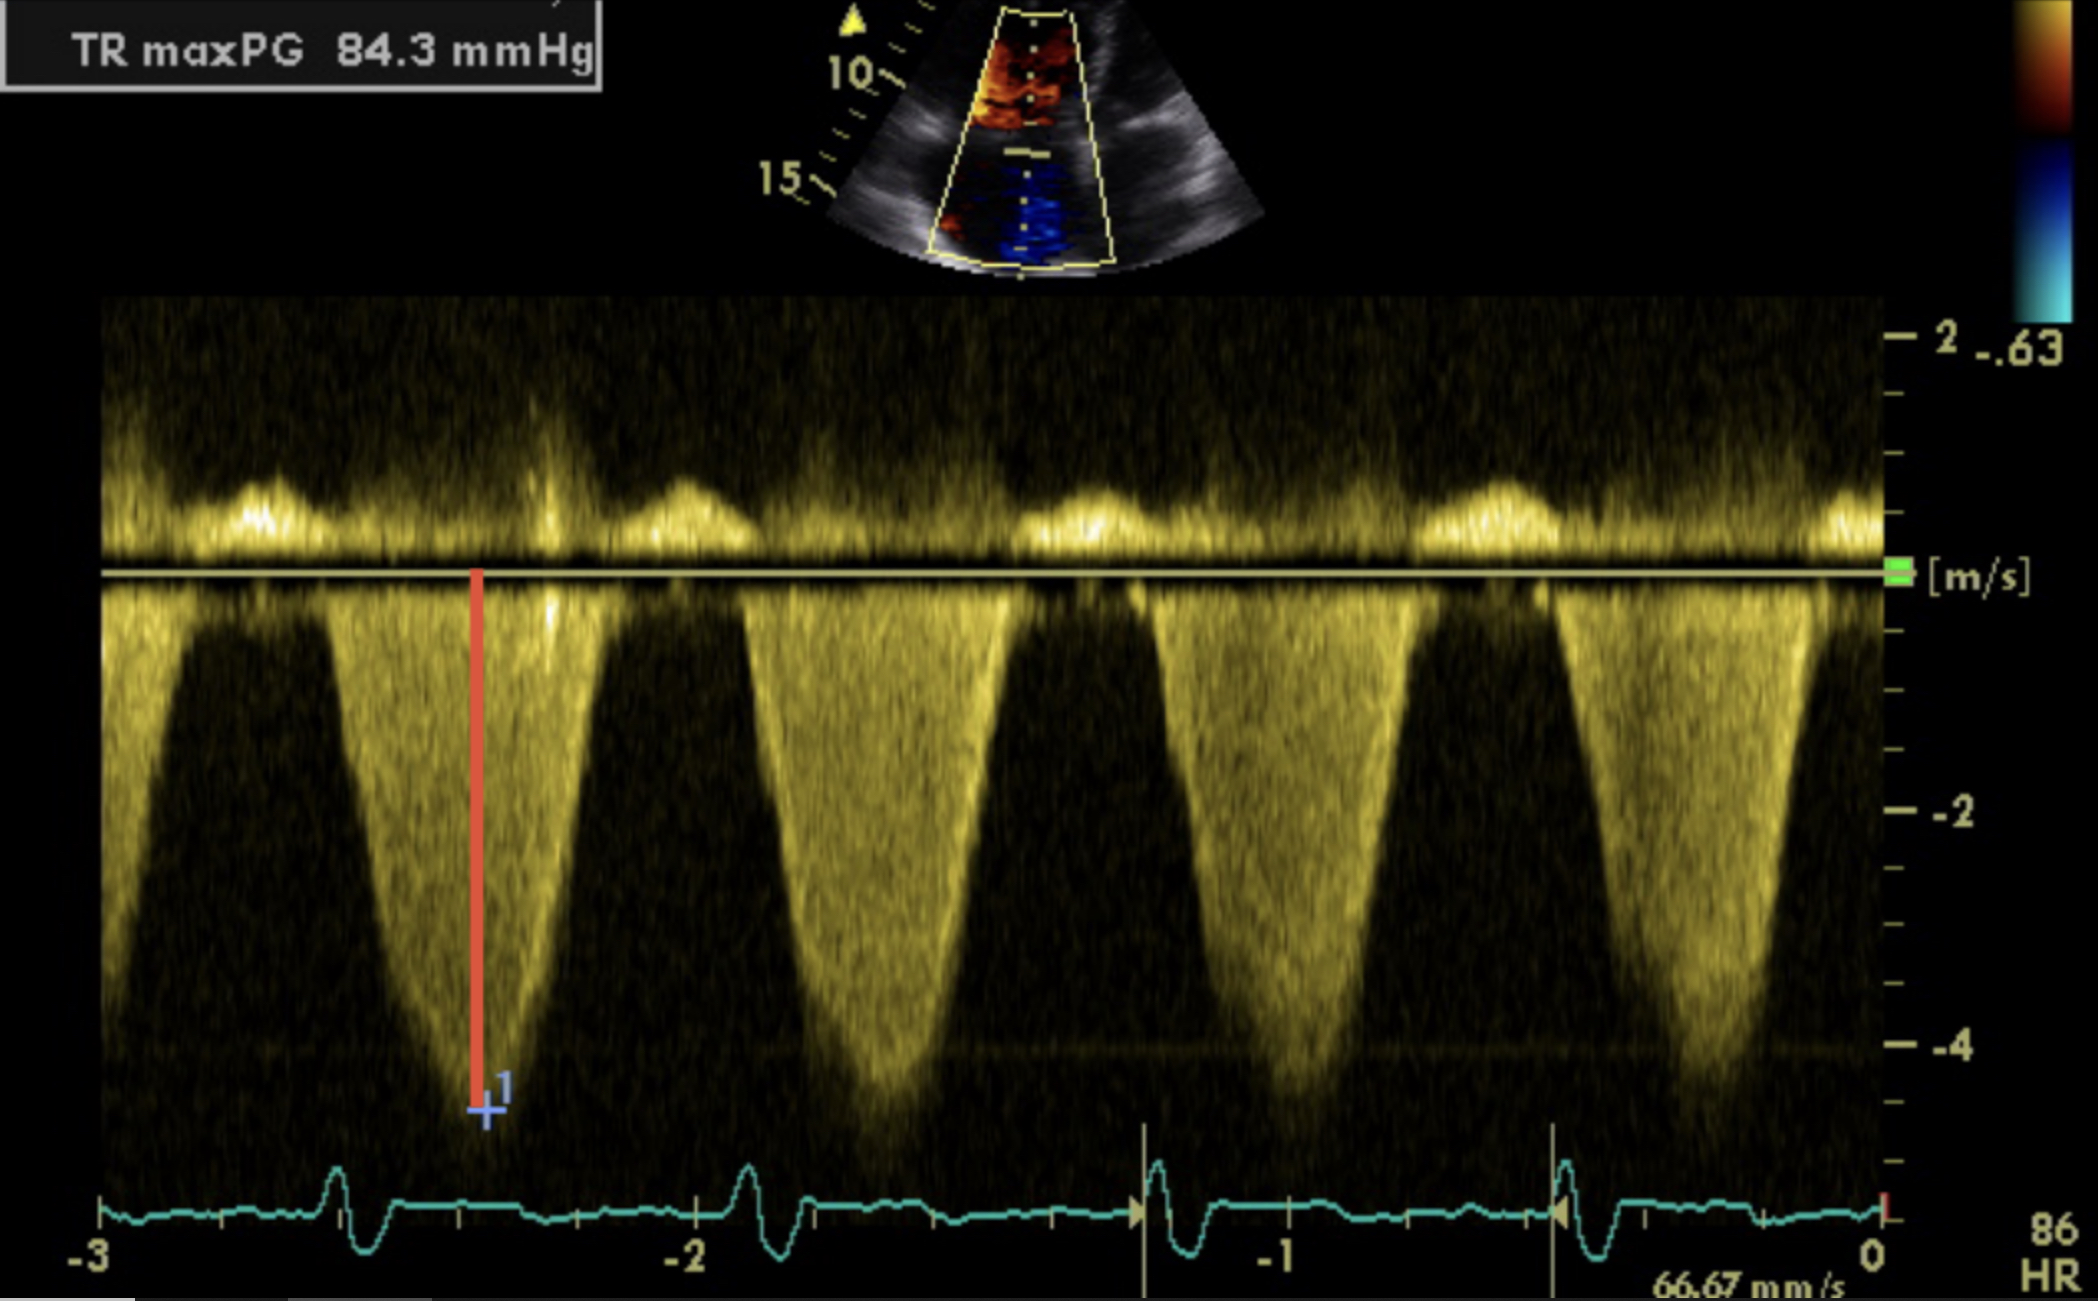

Worked in partnership with Janssen and US2AI on the diagnostic accuracy of automatic echocardiography measurements in the detection of pulmonary hypertension, alongside other cardiothoracic projects.